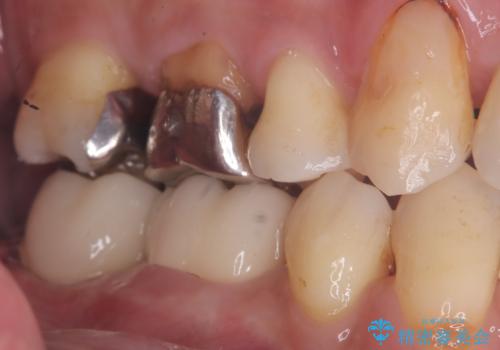

- 主訴:銀歯の入っている歯の側面に穴が空いている気がする。そこに食べ物が詰まる。

右上6番目の歯の被せものと歯質の境目に大きな窪みが出来ており、そこに汚れが停滞しやすい状態で虫歯もそこから広がっていたため、被せもののやり替えと必要に応じて土台の立て直しも行うこととしました。

メタルクラウンを除去したところ近心面に大きな窪みとう蝕を認め、ファイバ-コアからのやり替えとしました。クラウンは審美性の良いセラミッククラウンを選択されました。